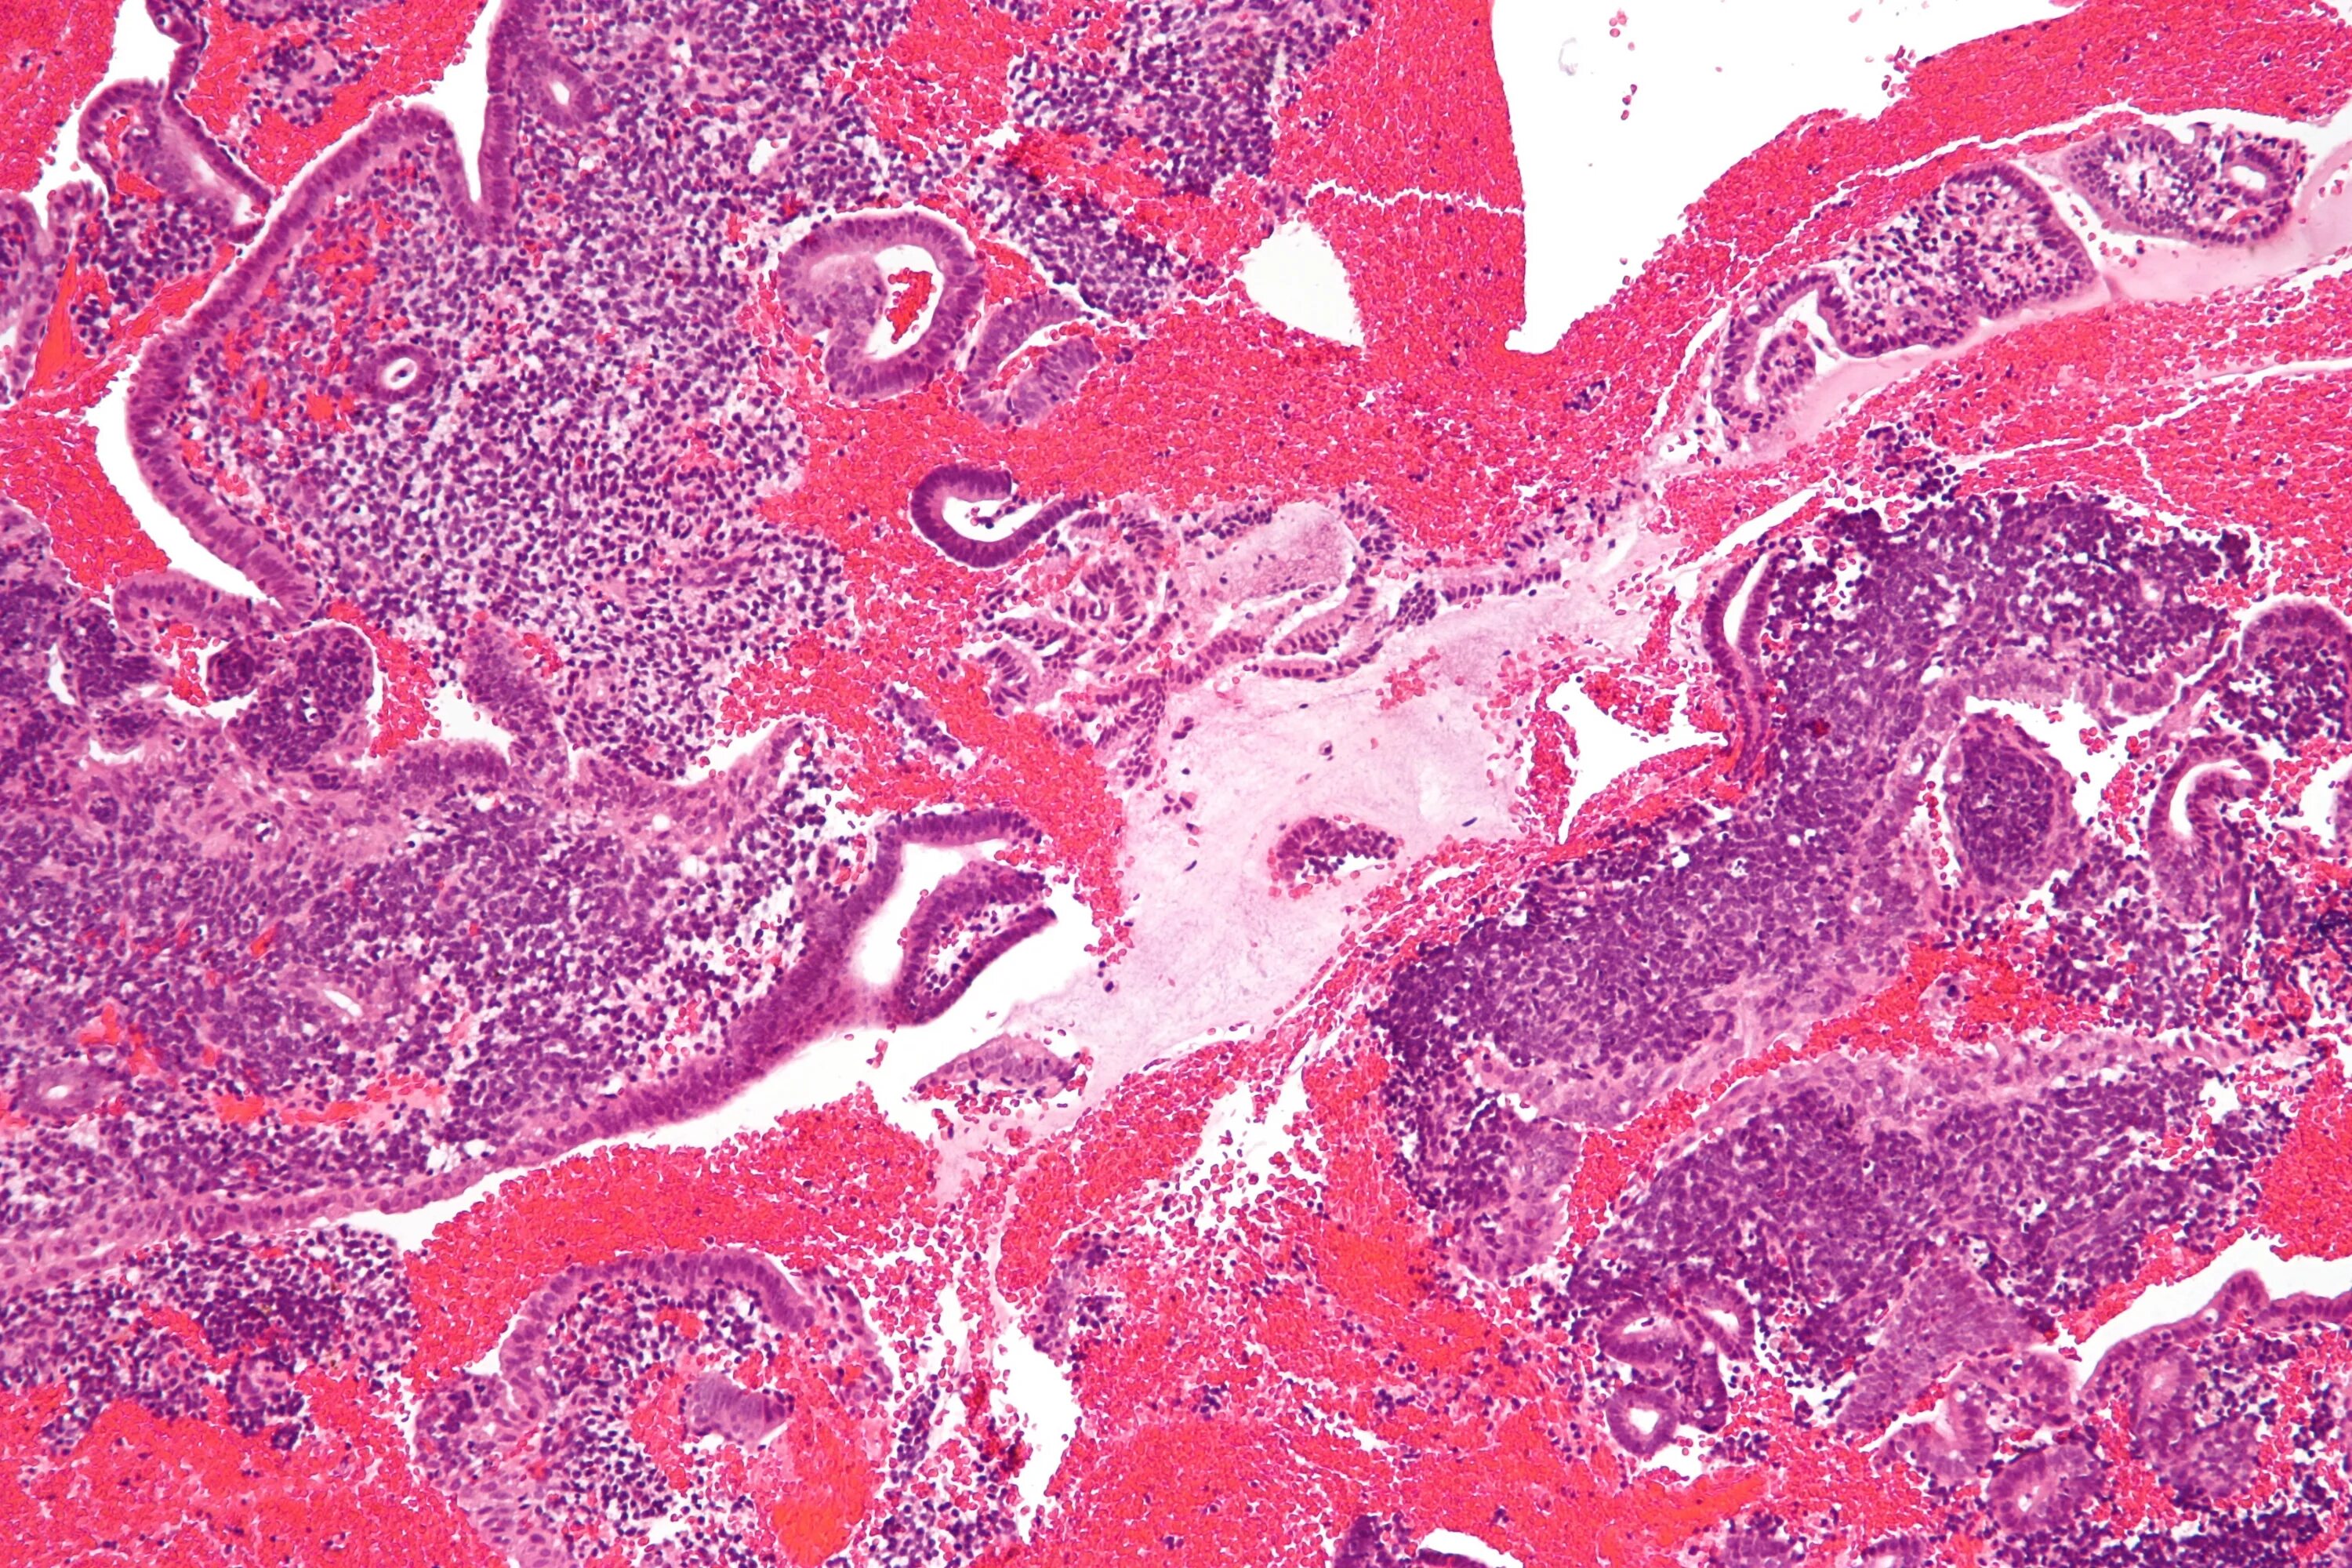

Гистологический соскоб